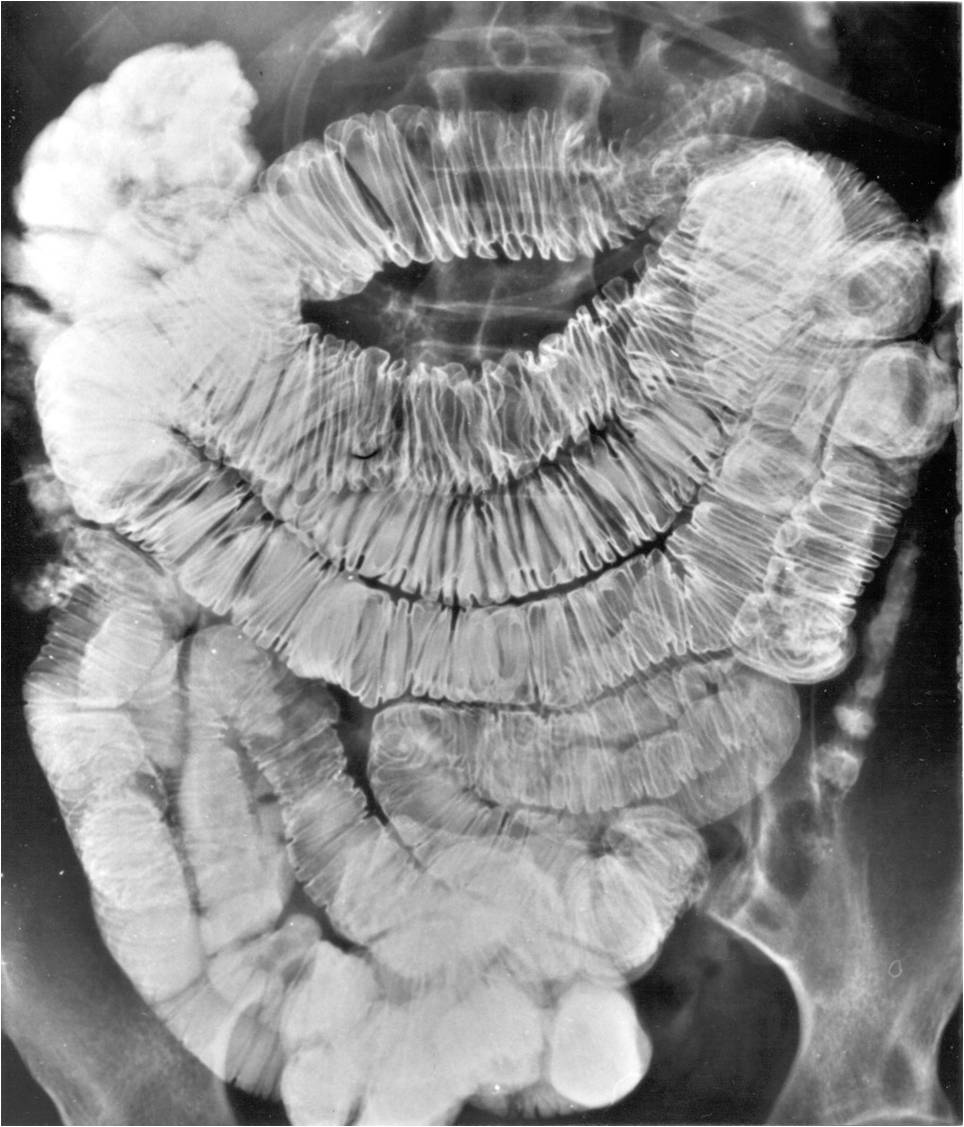

Image

Fig.20.: Follow-through examination

On the abdominal radiograph distension of the small bowel loops and air-fluid levels can be identified. It is important to describe forwarding of the contrast media by time or if mechanical obstruction is seen. Morphology of the intestinal loops could not be assessed with this method. This study is specifically conducted to examine the transit function only.